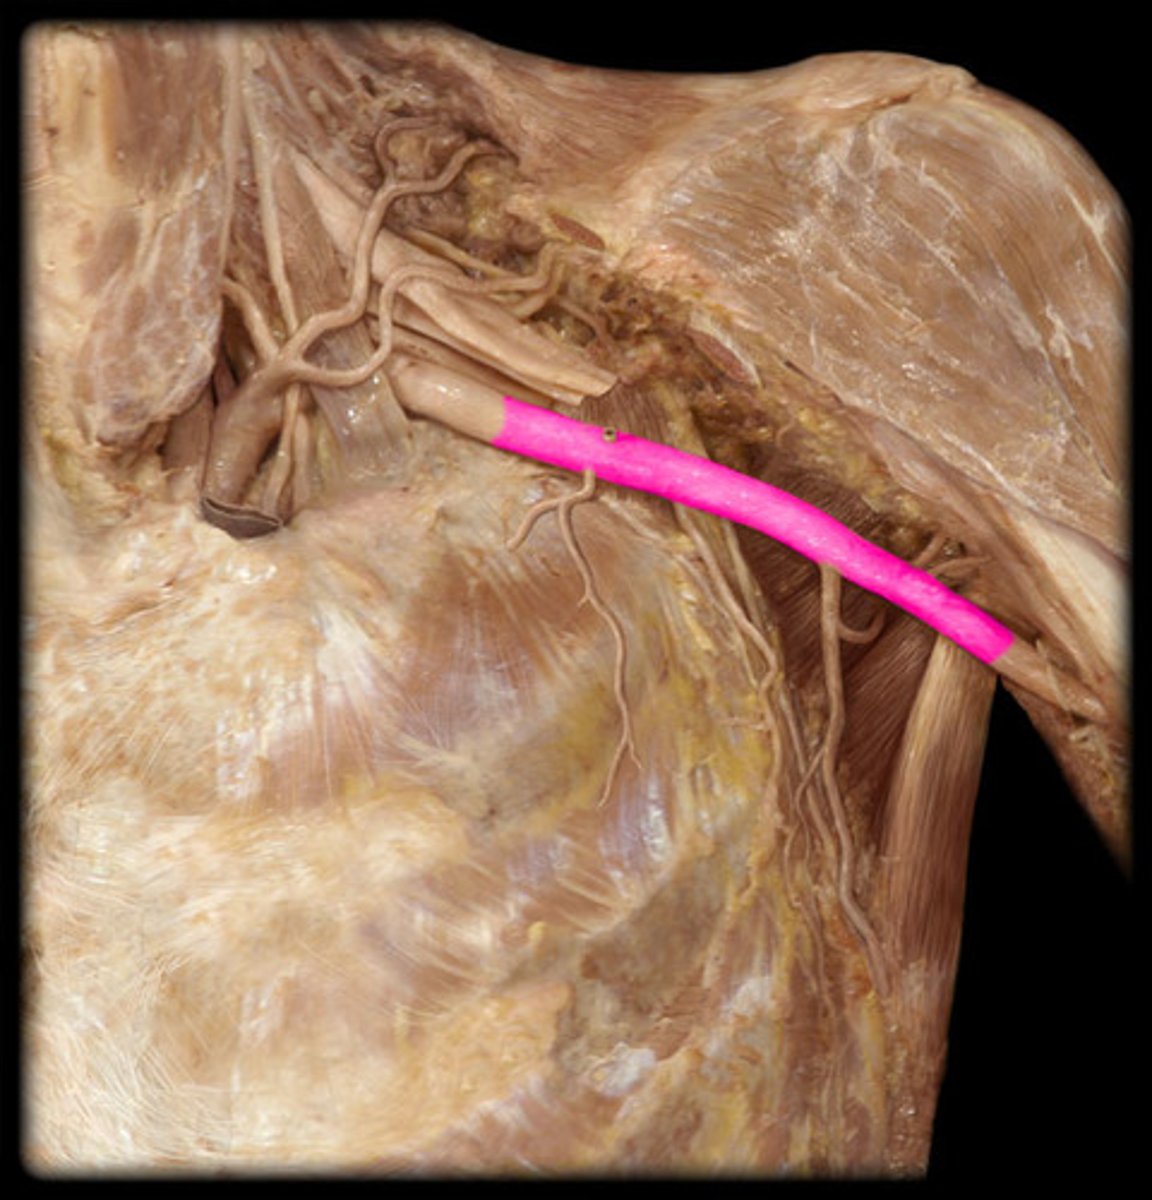

Axillary artery